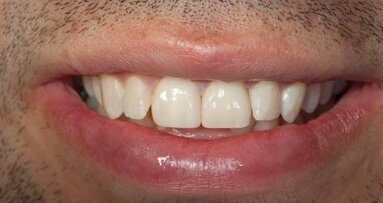

A 24-year-old female patient in excellent medical and good dental health presented stating she had not been to the dentist in some time and wished to improve her oral health and the appearance of her teeth. The pa­tient was unhappy with the shape and shade of her teeth. She was particularly concerned with the im­proper proportions of the width-to-length ratios of her incisors and the diastema present between teeth #11 and 21 (Figs. 1 & 2).4 Several areas of gingival asymmetry were also noted. The patient stated that she had re­ceived orthodontic treatment in the past, and cos­metic bonding (which had already failed at the time of her presentation) to close the diastema between teeth #11 and 21. She expressed her desire to have a beautiful, brighter and natural-looking smile.

Fig. 1: Pre-op full smile.